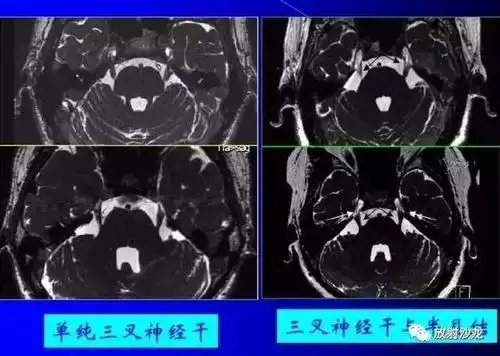

继发性三叉神经痛患者头颅mri 强化扫描,可见增粗的三叉神经三叉神经

患者头颅mri 强化扫描,可见增粗的三叉神经三叉神经鞘瘤伽玛刀后明显